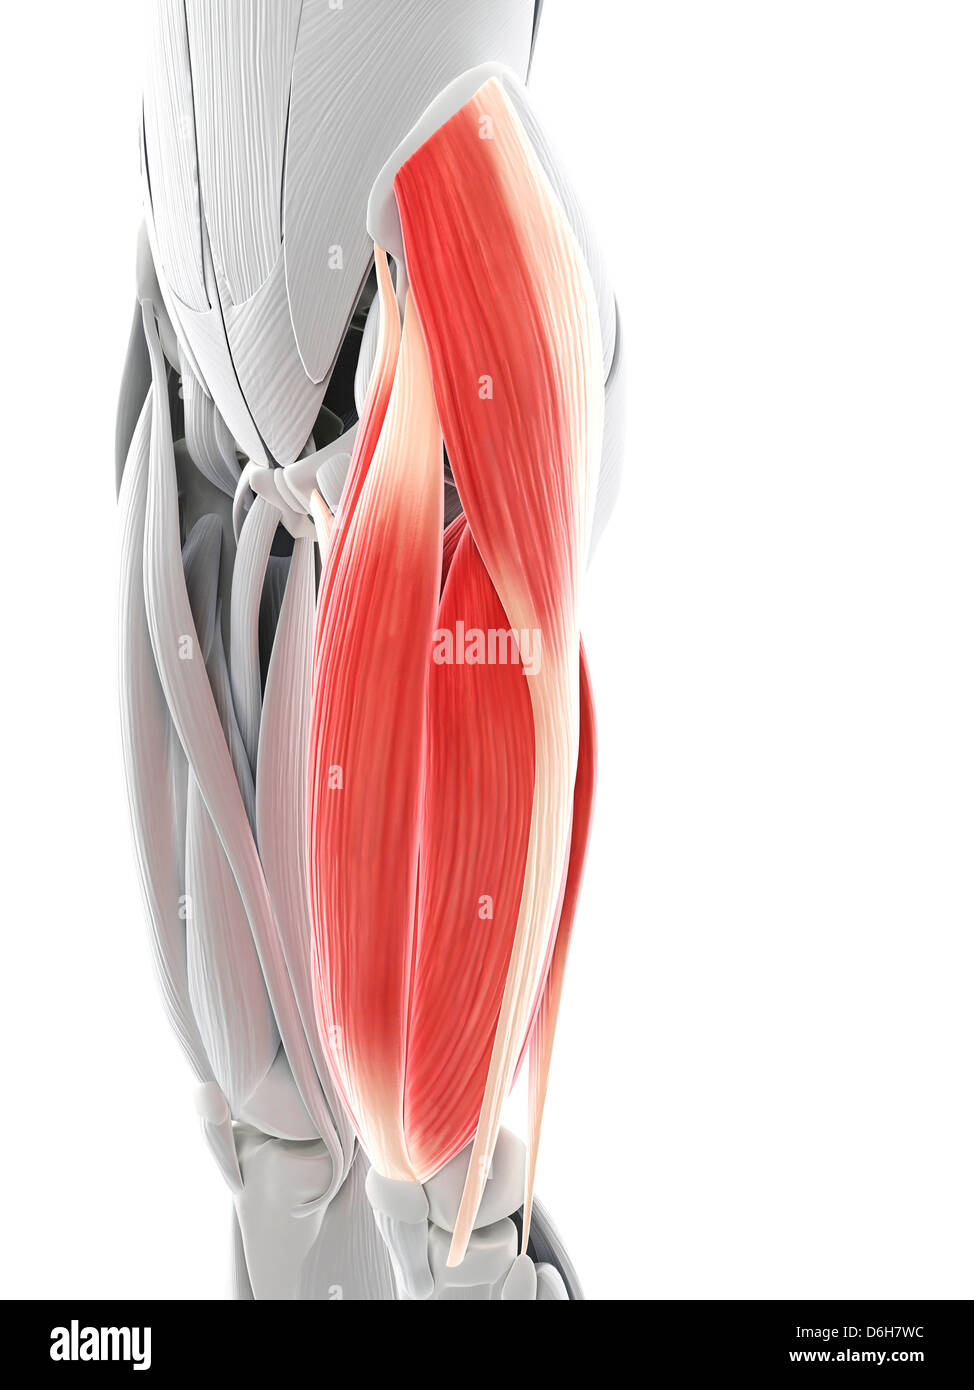

La cuisse, artwork Banque D'Imageshttps://www.alamyimages.fr/image-license-details/?v=1https://www.alamyimages.fr/photo-image-la-cuisse-artwork-55699139.html

La cuisse, artwork Banque D'Imageshttps://www.alamyimages.fr/image-license-details/?v=1https://www.alamyimages.fr/photo-image-la-cuisse-artwork-55699139.htmlRFD6H8PY–La cuisse, artwork